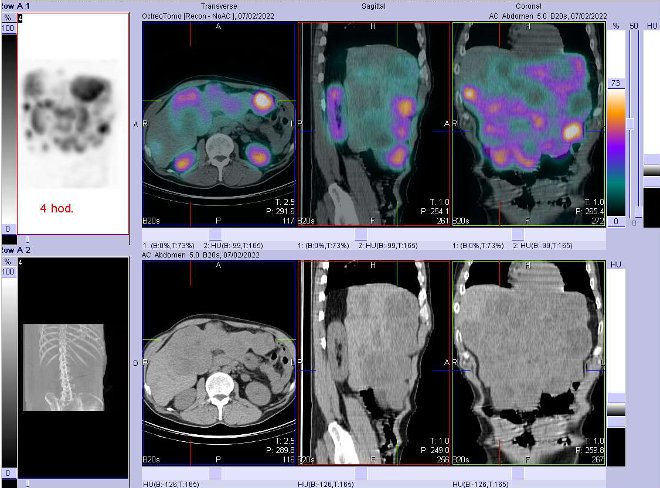

Pomocí dvoudetektorové hybridní tomografické kamery Symbia T2 (SPECT/CT) firmy Siemens opatřené kolimátory pro střední energie jsme provedli celotělovou scintigrafii a také cílenou tomografickou scintigrafii (SPECT) a CT a fúzi obrazů SPECT/CT břicha a pánve za 4 a 24 hod.

(obr. 1-7) po i.v. podání 220 MBq analogu somatostatinu značeného

111In (přípravek OctreoScan firmy Mallinckrodt Medical).

/ Obr. č. 2: Fúze obrazů SPECT a CT – vyšetření 4 hod. po aplikaci radiofarmaka. Zaměřeno na ložisko v pravém jaterním laloku.

/ Obr. č. 3: Fúze obrazů SPECT a CT – vyšetření 4 hod. po aplikaci radiofarmaka. Zaměřeno na ložisko v pravém jaterním laloku.

/ Obr. č. 4: Fúze obrazů SPECT a CT – vyšetření 4 hod. po aplikaci radiofarmaka. Zaměřeno na ložisko v pravém jaterním laloku.

Závěr: Za 4 a 24 hod. jsou patrná mnohočetná různě velká patologická ložiska vyšší depozice radiofarmaka nepravidelného tvaru v játrech a navíc mnohá ložiska naopak s defektem v depozici radioaktivity

- zřejmě tedy nekrotická. Játra jsou enormně zvětšená, abnormálního tvaru, největší vertikální rozměr 26 cm, dolním okrajem zasahují až do pravého hypogastria a k úrovni pravé kosti kyčelní.

Závěr: obrovská játra s mnohočetnými různě velkými ložisky nepravidelného tvaru jak se zvýšenou depozicí radiofarmaka, tak naopak s defekty v depozici

- s nekrózami. Nález svědčí pro mnohočetná ložiska se zvýšenou denzitou somatostatinových receptorů

- pro ložiska neuroendokrinního tumoru.